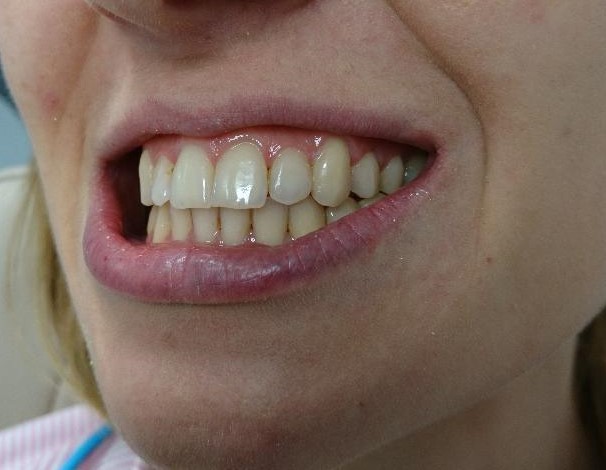

Pacient, 26 ani. Caz nonextracționist, Expander Maxilar + aparate ortodontice fixe bimaxilare.